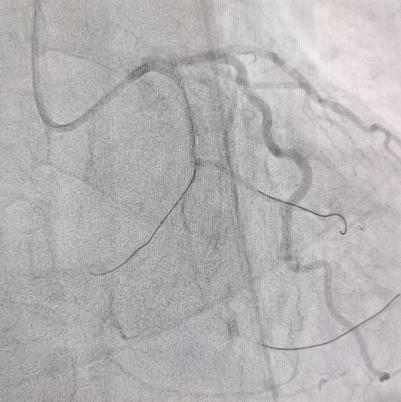

术中

术后